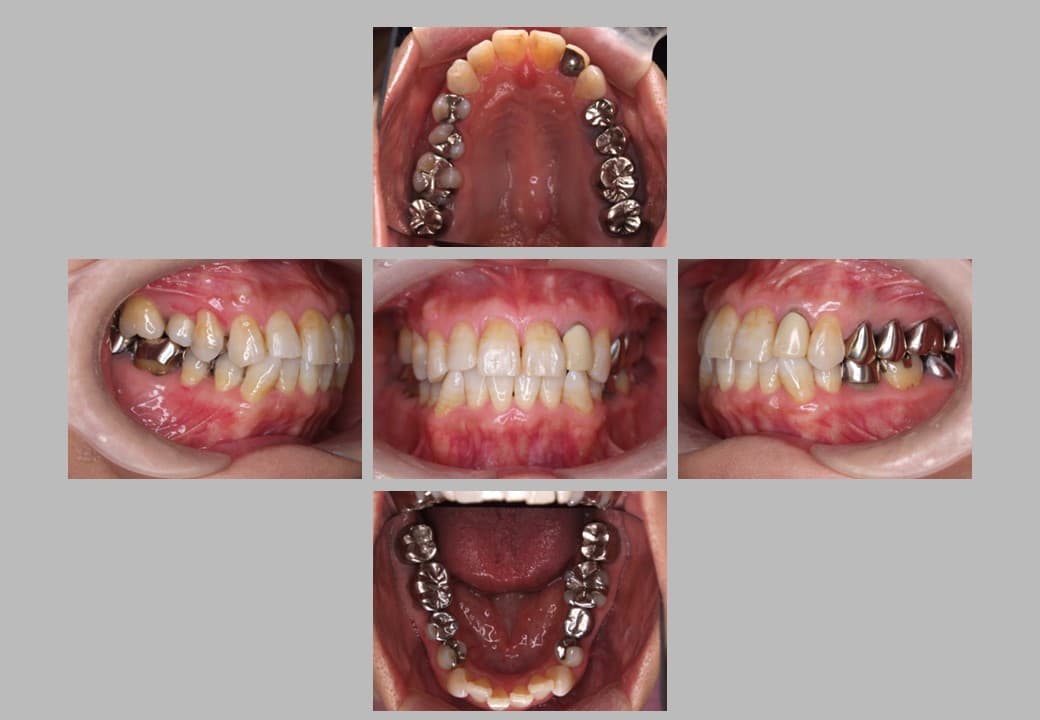

セラミック治療 (メタルフリー治療)の症例紹介②

治療希望:金属の被せ物をセラミックにしたい

治療内容:セラミック治療

治療期間:約6ヶ月

治療後

セラミック治療の実施事例です。